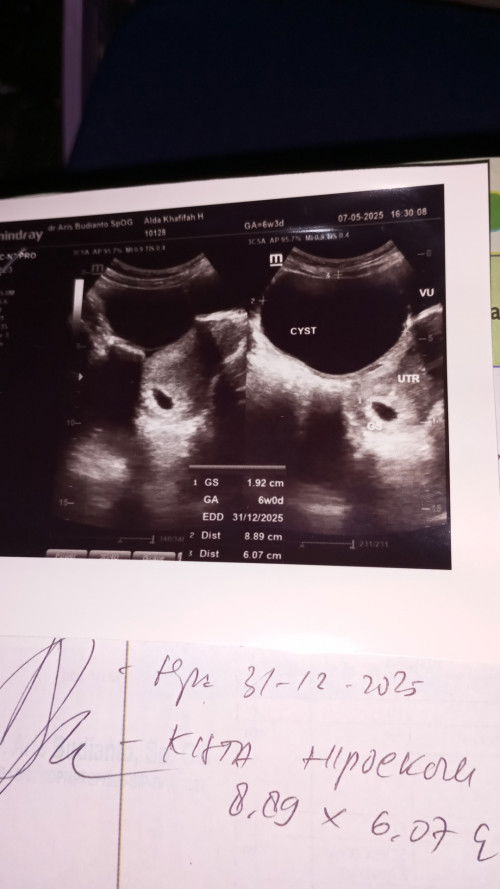

Kista 9 cm

Ada yang sama? Lagi hamil 6 week trnyta ada kista nya juga 9 cm. Tapi ak gak ada keluhan apa2 cuma kram perut kadang2. Kemarin pas usg trnyta baru kantongny aja, aman gasi ada kista besar giniđ¤đ¤

Tdi aku usg kaget trnyta ada kista ukuran 8,89 cm. Tapi kata dokter selama gk ganggu kehamilan sih aman. Ad yg sama?